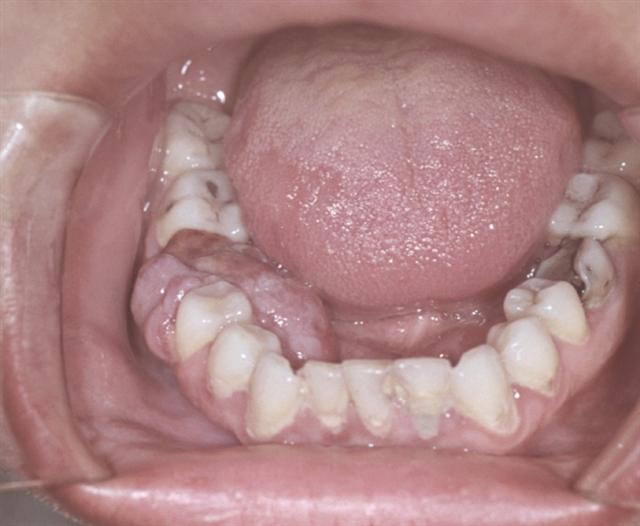

Рис. 3. Гигантоклеточный эпулис: бугристое образование — преимущественно на внутренней поверхности нижней челюсти, охватывает область удаленного зуба.